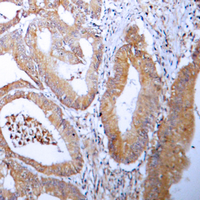

IHC (Immunohiostchemistry)

(Immunohistochemical analysis of ACC alpha staining in human colon cancer formalin fixed paraffin embedded tissue section. The section was pre-treated using heat mediated antigen retrieval with sodium citrate buffer (pH 6.0). The section was then incubated with the antibody at room temperature and detected using an HRP conjugated compact polymer system. DAB was used as the chromogen. The section was then counterstained with haematoxylin and mounted with DPX.)